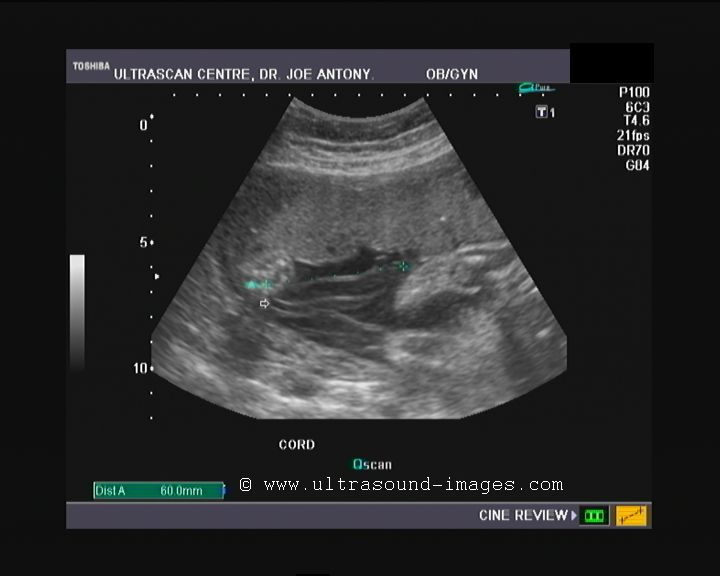

Case-3: Hypocoiled umbilical cord

This early 3rd trimester fetus showed a markedly hypocoiled cord. The intercoil distance here is more than 8 cms. Hence the UCI or umbilical coiling index is= 1/8 which is less than 0.12. (very low).